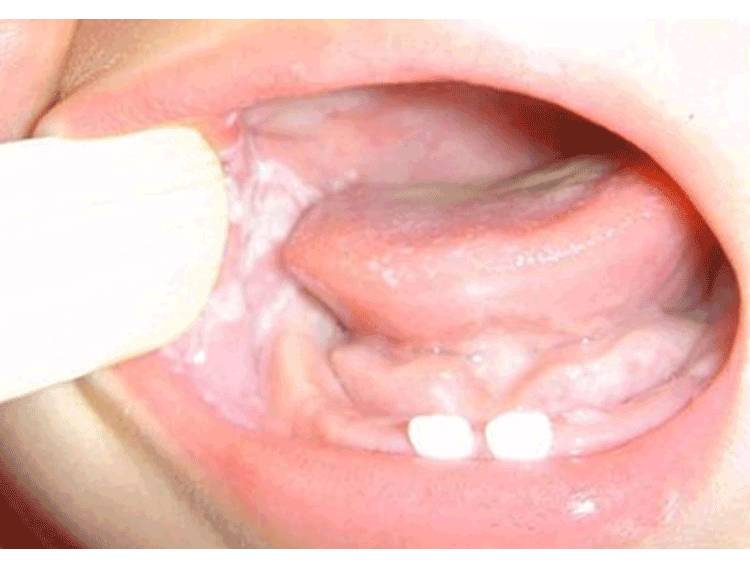

鹅口疮,婴幼儿时期宝宝最长常见的一种疾病,由于患有鹅口疮的宝宝会在舌上、颊内、牙龈或上颚散布白屑,融合成片,因此又称之为雪口病。

如果你家宝宝在喂奶时总是哭闹不止,口腔两侧和舌头黏膜上有白色的斑点那很有可能就是得了鹅口疮哦。

发现白色斑点后妈妈们可以先用棉签沾上温水轻轻拭去,鹅口疮往往擦除困难,擦除后会留有红色创口,排除是奶块的可能。